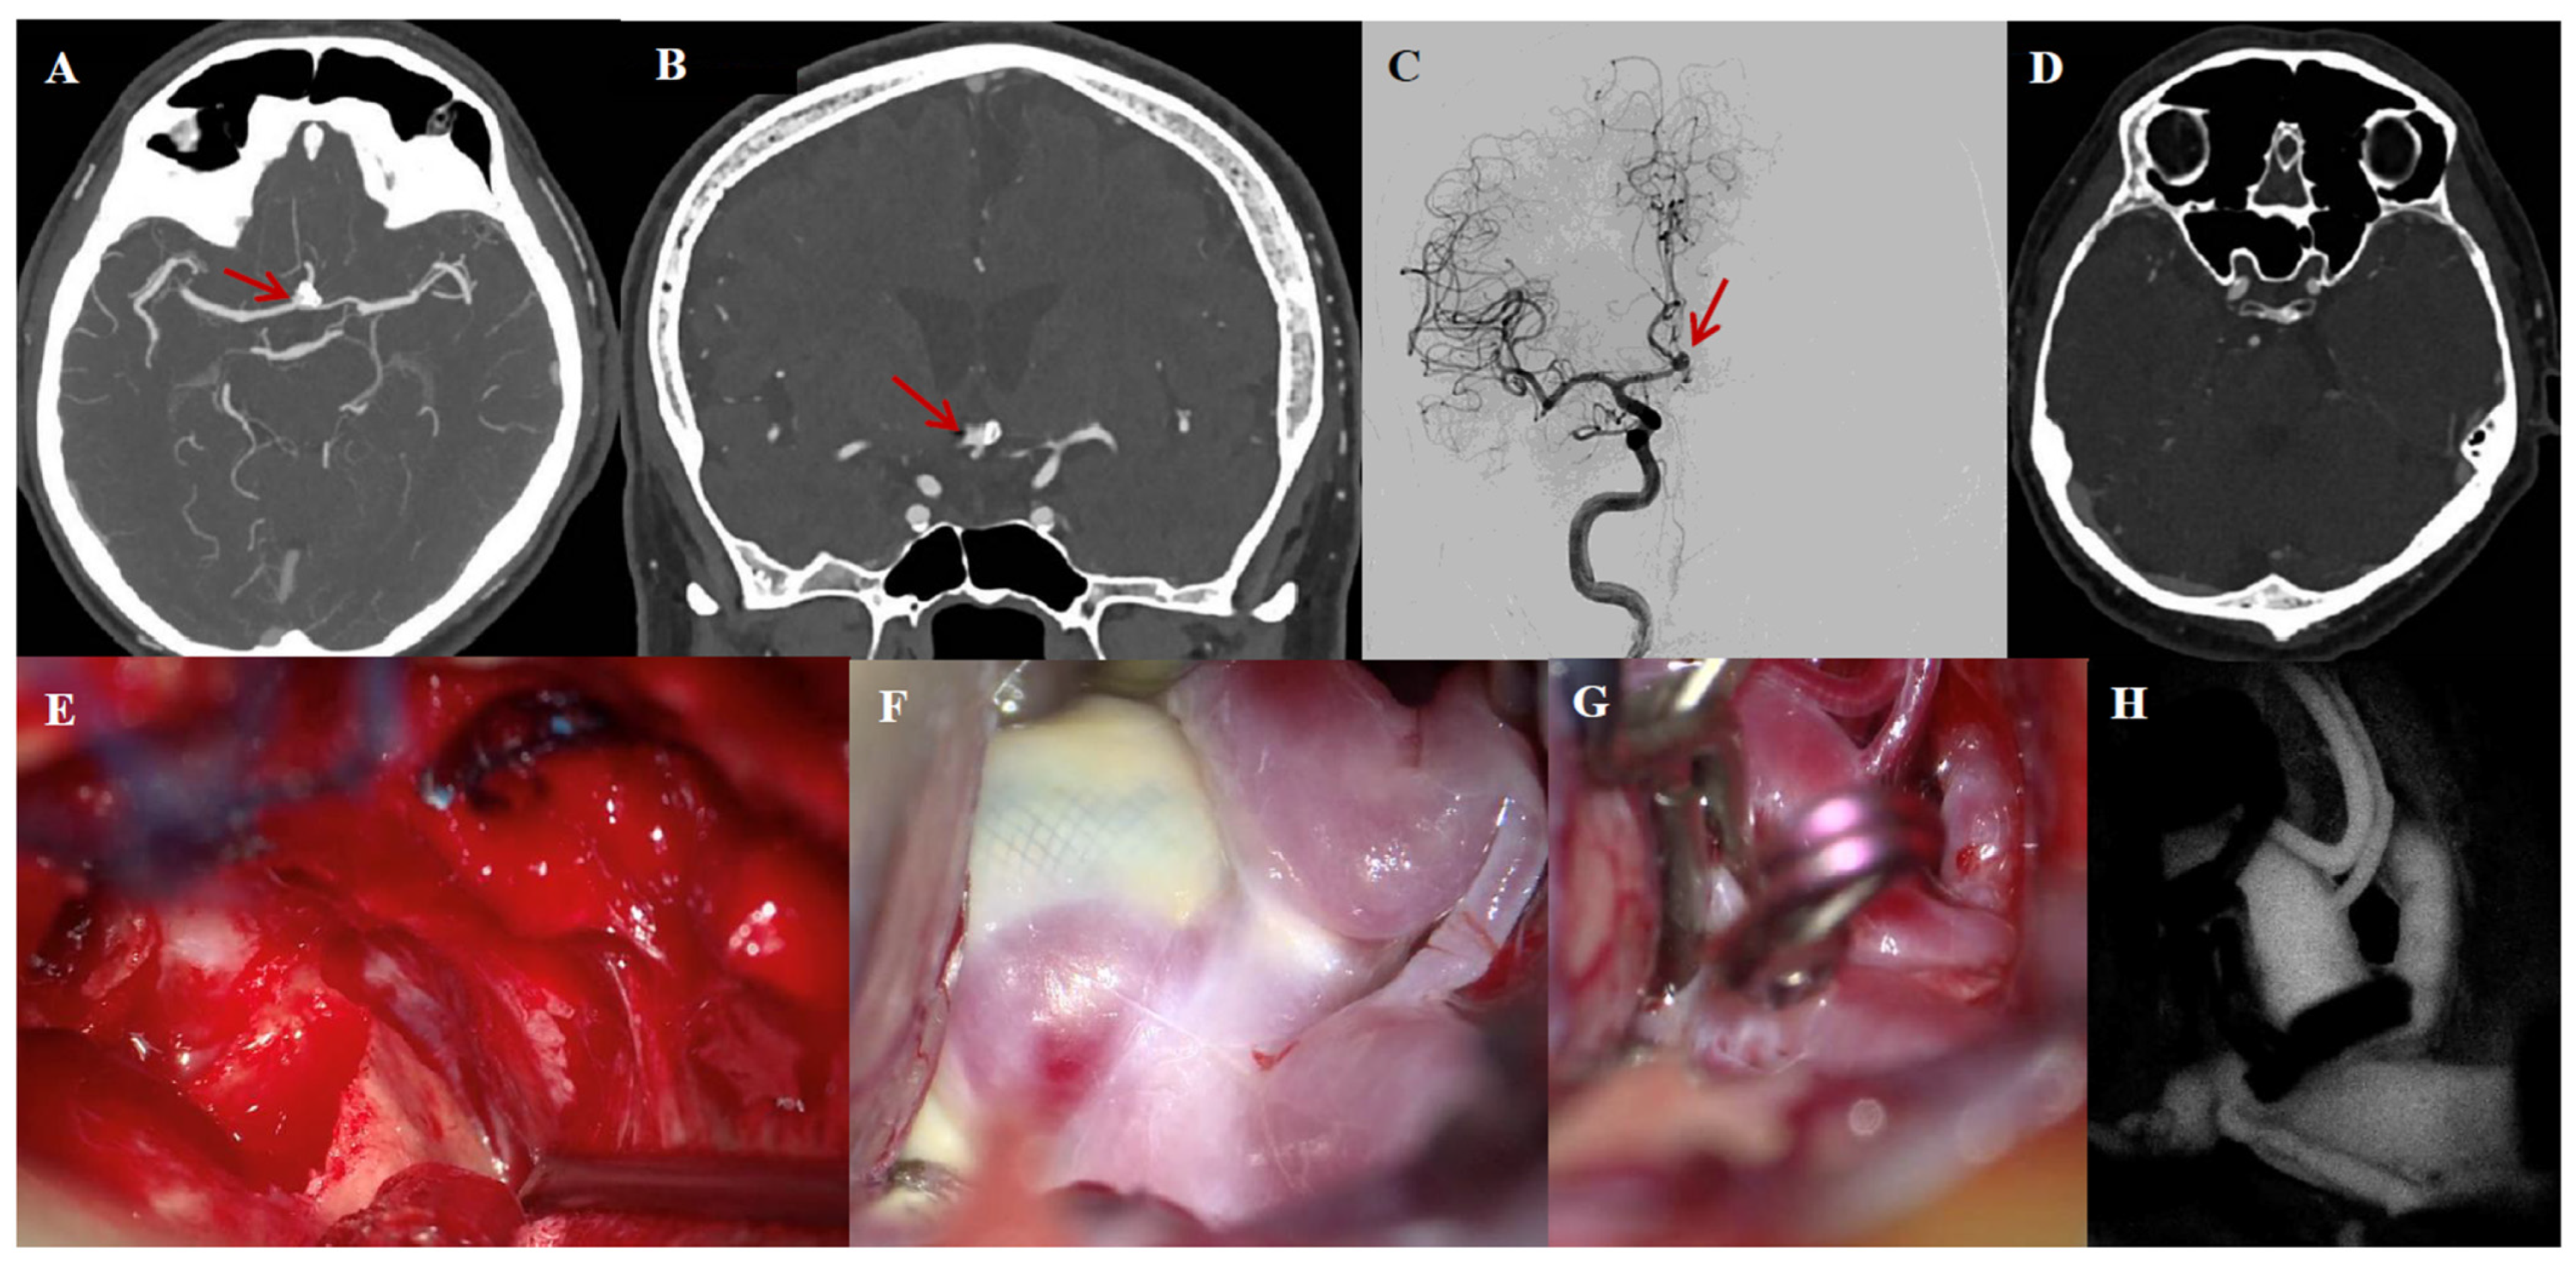

3.6. Illustrative Case #2